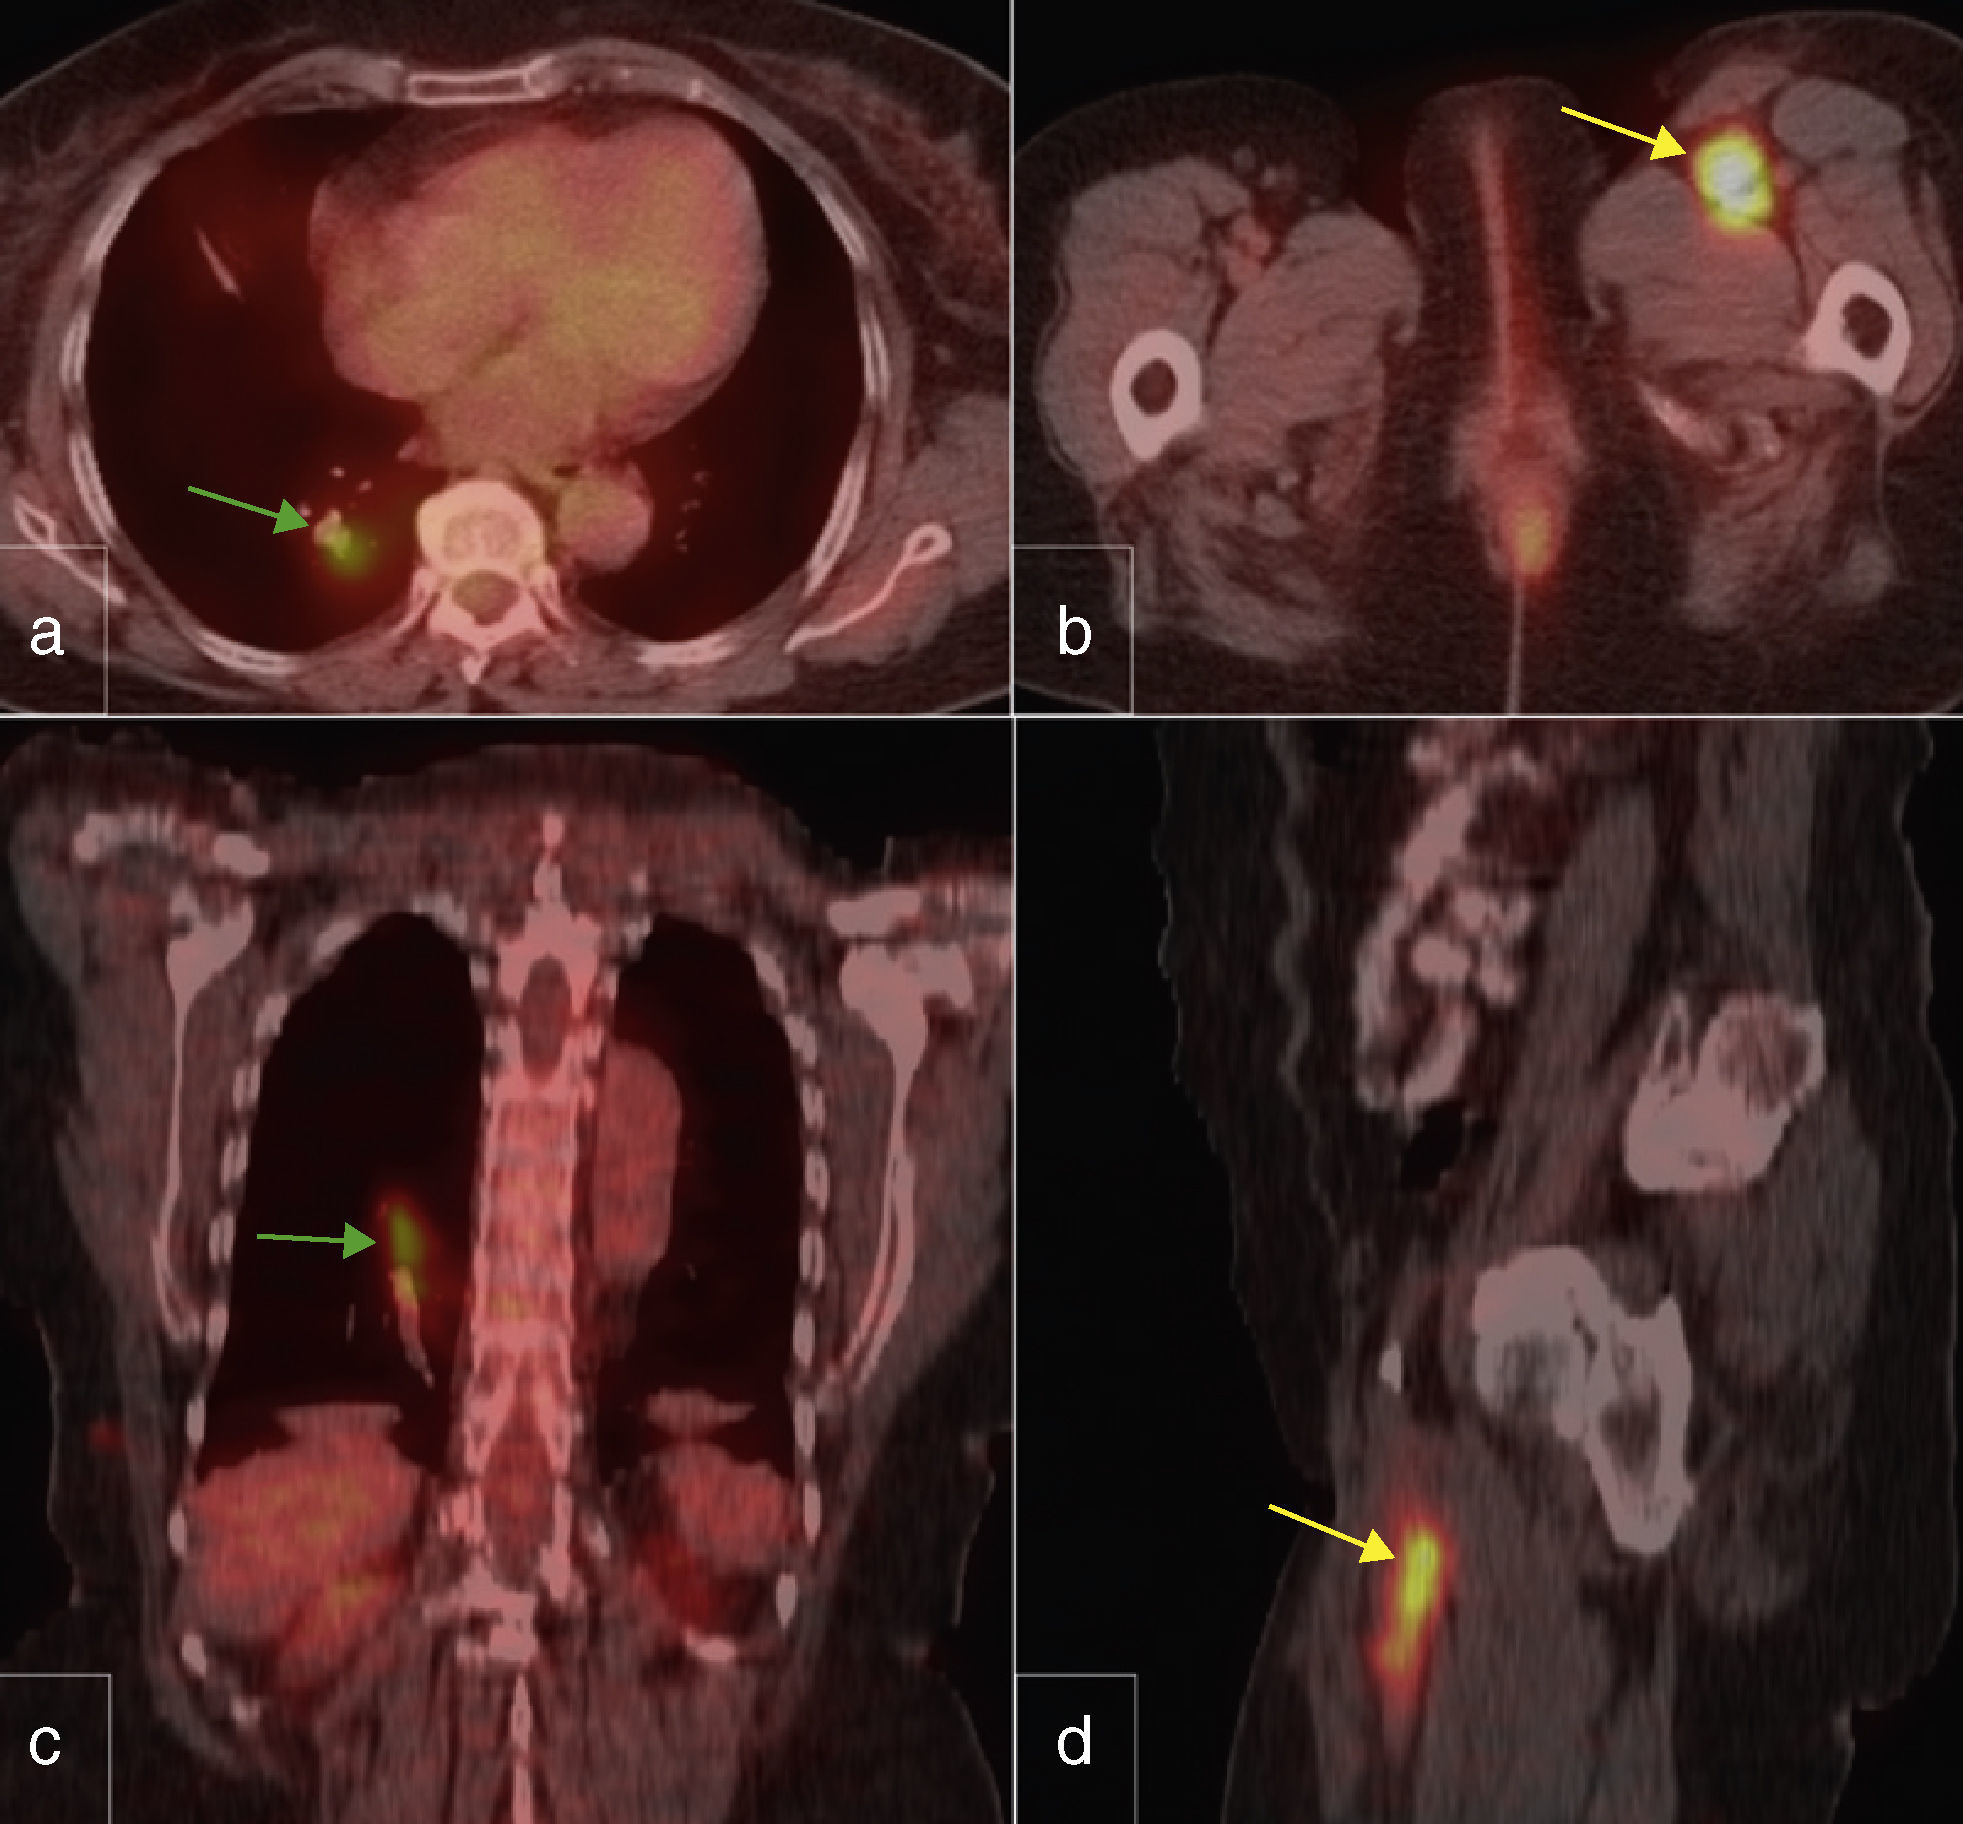

Tumor thrombosis detected on PET/CT scanning in a patient with metastasic melanoma

Trombosis tumoral detectada en el estudio PET/TC en un paciente con melanoma metastático